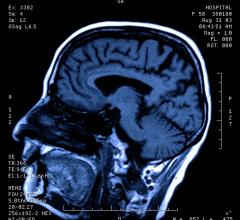

Technology Report:

Computed Tomography (CT)